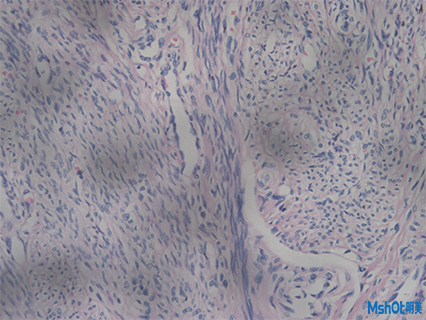

病理切片取一定大小的病变组织,用病理组织学方法制成病理切片。病理切片是透明的,在显微镜下能够观察到组织的形态,搭配显微镜相机可对观察到的形态效果图进行保存对比,拼接等操作,通过病变的发生发展过程,作出病理诊断。

近日,深圳某医疗科技公司在网上找到我们,客户已有一台奥林巴斯倒置显微镜IX71,需要配一套高像素显微镜相机拍病理切片和荧光切片,深圳区域工程师根据老师实际需求推荐了明美科研级显微镜相机MSX2,这款显微镜相机采用大靶面高性能的成像芯片,设计USB3.0数据传输接口,具有高分辨率、颜色还原准确和高灵敏度的特点,其色彩表现,是液基细胞分析、免疫组化、骨髓细胞分析等对颜色要求高的病理诊断的理想工具。此外在明暗场、相衬、偏光、DIC、荧光成像等领域同样适用。